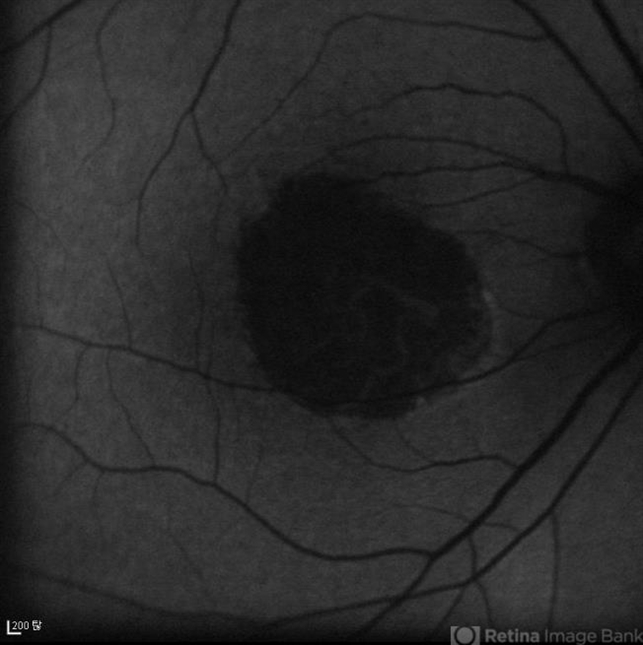

- Geographic atrophy

- geographic atrophy, dry age-related macular degeneration (dry AMD)

- FAF image of an 78-year-old woman. Her best-corrected visual acuity was counting fingers at 30cm.